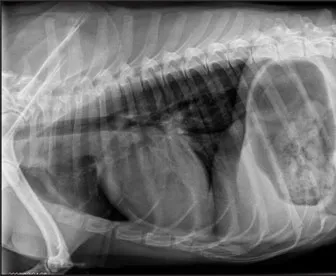

CASE 1.3 An 8-year-old male German Shepherd Dog with lethargy and muffled heart sounds. No heart murmur ausculted. You obtain these thoracic radiographs: Fig. 1.3a, left lateral projection; Fig. 1.3b, dorsoventral projection.

1 What are your radiographic findings?

2 What is your radiographic diagnosis?

3 Is additional imaging needed?

1.3a

1.3b